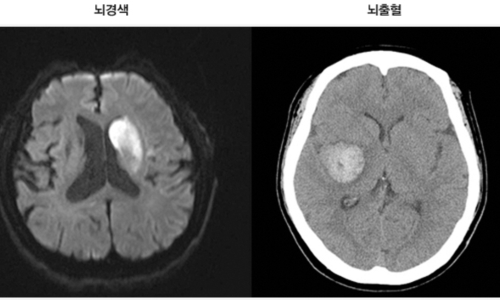

뇌혈관이 막히거나 터지는 질환을 통칭하는 것이 뇌졸중이고 그 중 뇌혈관이 막히는 것이 뇌경색 그리고 뇌혈관이 터지는것을 뇌출혈이라고 합니다. 뇌졸중은 영구적인 손상이 많고 증상에 따라 전신이나 신체 일부 기능이 마비되는 등의 심각한 후유증이 남는 무서운 질병인데요 오늘은 뇌경색 초기증상 및 뇌경색 치료방법에 대해 알려드리겠습니다.

신체가 건강해도 뇌에 문제가 생기게 되면 신체 기능을 제대로 할 수가 없게 됩니다. 뇌 손상으로 제한된 신체 기능은 치료를 마친 후에도 회복이 제대로 되지 않거나 장애로 남는 경우가 많은데 뇌조직이 괴사되며 발생하게 되는 뇌경색이 대표적입니다. 과거에는 뇌출혈 환자가 많았지만 현재는 전체 뇌졸중 환자의 약 60~70%가 뇌경색 환자인 만큼 뇌졸중에서도 뇌경색이 차지하는 비중이 크다고 합니다.

뇌졸중에서도 혈관이 막히는 뇌경색이야말로 촌각을 다투는 응급질환이라고 볼 수 있습니다. 뇌혈관이 막히면서 점차 뇌세포가 괴사하기 때문에, 증상 발현 3시간 안에 혈전용해제를 투여하고 시술에 들어가야 심각한 상황을 면할 수 있습니다. 뇌경색 치료방법에 있어 가장 중요한 것은 혈전을 녹이는 혈전용해제를 정맥 투여함으로써 막힌 혈관을 뚫어주는 것입니다. 하지만 혈전용해제의 경우도 출혈 가능성이 있는 환자에게는 투여할 수 없으며, 또한 혈소판 수치가 낮아서 지혈이 되지 않는 경우에는 제외된다고 합니다.

또한 과거에 이미 뇌출혈이 발생한 경우와 고혈압 환자의 경우도 혈전용해제를 투여할 수 없다으며 보통은 약50% 정도의 환자에게만 혈전 용해제를 이용한 치료가 가능합니다. 막힌 혈관을 뚫어주는 치료를 한 이후에도 뇌경색은 꾸준히 관리해야 하는데 재발할 확률이 높기 때문입니다. 따라서 약물치료와 함께 재활 치료가 필요하며 치료 이후 초기에 재활 치료를 적극적으로 해야 뇌경색 치료방법의 효과가 크고 후유증을 줄일 수 있습니다.